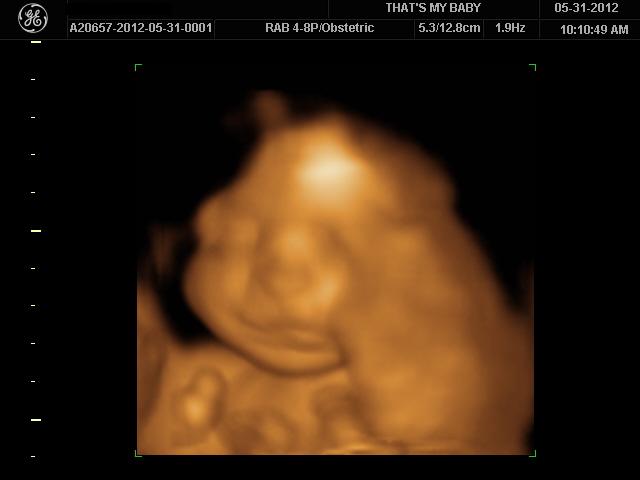

we had an elective 3D ultrasound this morning. I always thought they looked kinda alien-like, but I guess it's different when it's your own kid. Ronin, of course, was not cooperative in the slightest at first. he was sleeping like a rock and would not change positions... and when he did show his face, his put his hand up in front of it. he even put his hand in front of his face and FLICKED US OFF.

anyway, after moving around and poking him, we finally got some decent shots of his cute face. remember how my bump watch update said that he should be weighing about 2lbs? yeah, this chub weighs about 3lbs 10oz. the sonogram tech estimated that he will probably be over 8lbs at birth.

he has a large head (no surprise there... have you SEEN my husband's dome?), fat feet, and big hands. he's also got a pretty long torso, which is probably why he's weighing so much already... it also explains why I feel like he's cramped in there.

I may be biased, but I think he's pretty damn cute already! I can't wait to meet him! :D